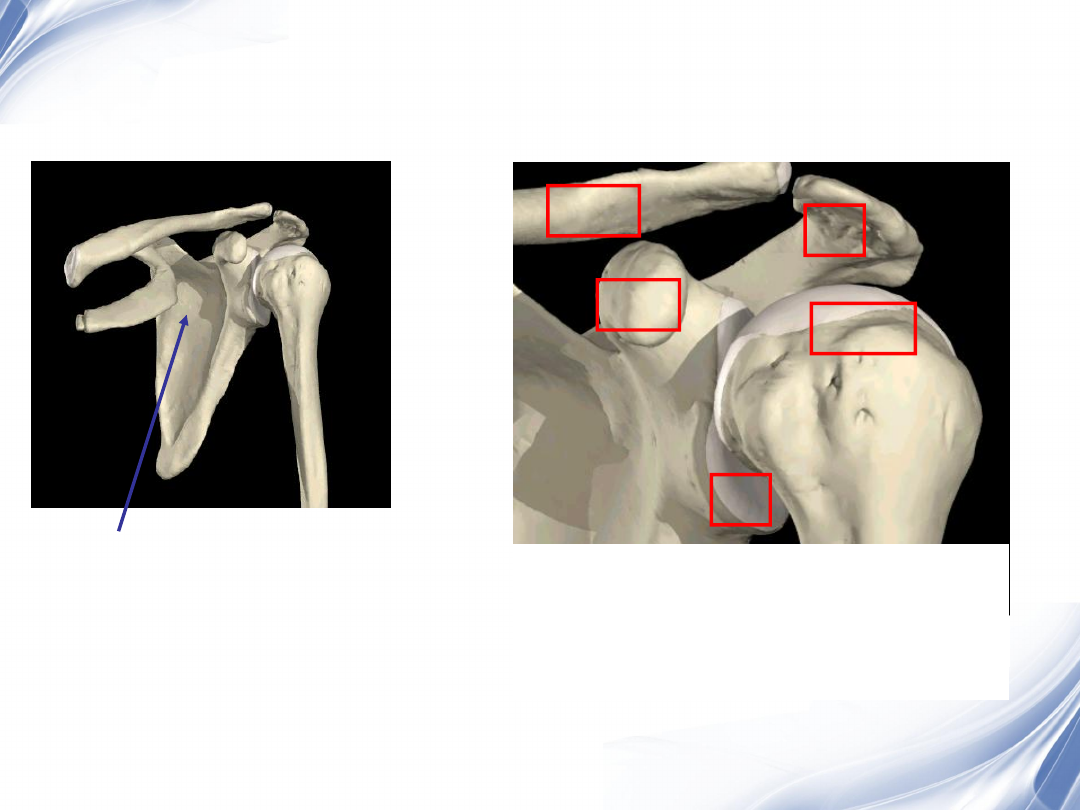

概述-定义

肩袖:由冈上肌、冈下肌、肩胛下肌及小圆肌之

肌腱在肱骨头前、上、后方形成的袖套样肌样结

保持肱盂关节稳定,维持上臂各种姿势和完成各

种运动功能。

• 冈上肌损伤最常见(约占70%)

肩袖的解剖

冈上肌肌腱

冈下肌肌腱

小圆肌肌腱

肩胛下肌肌腱